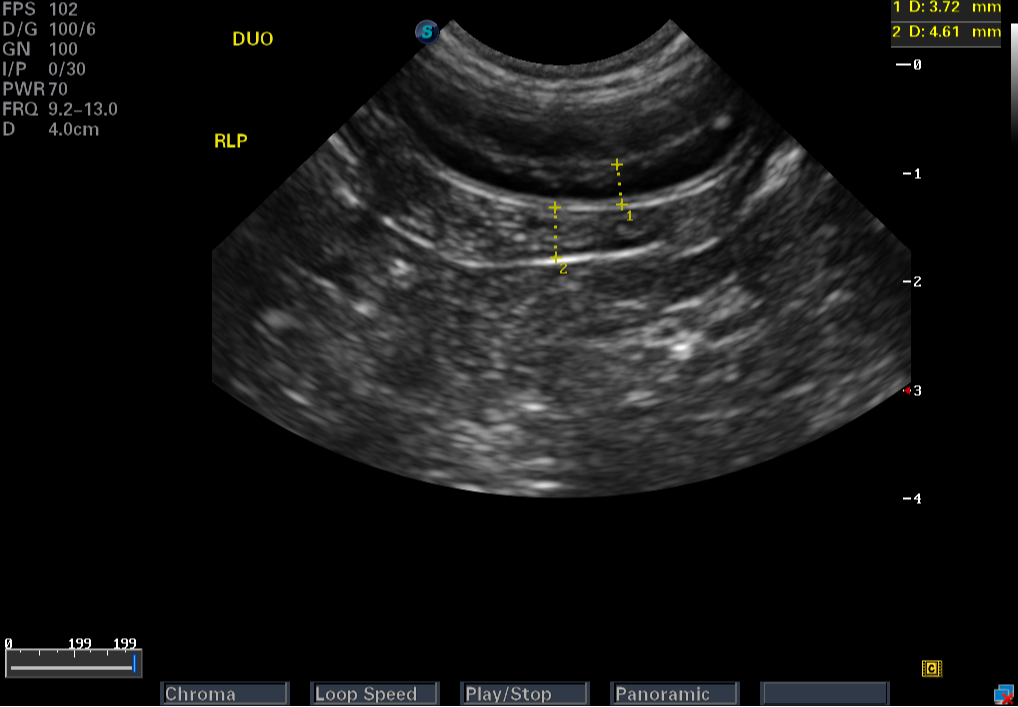

Images from the S9 Pro